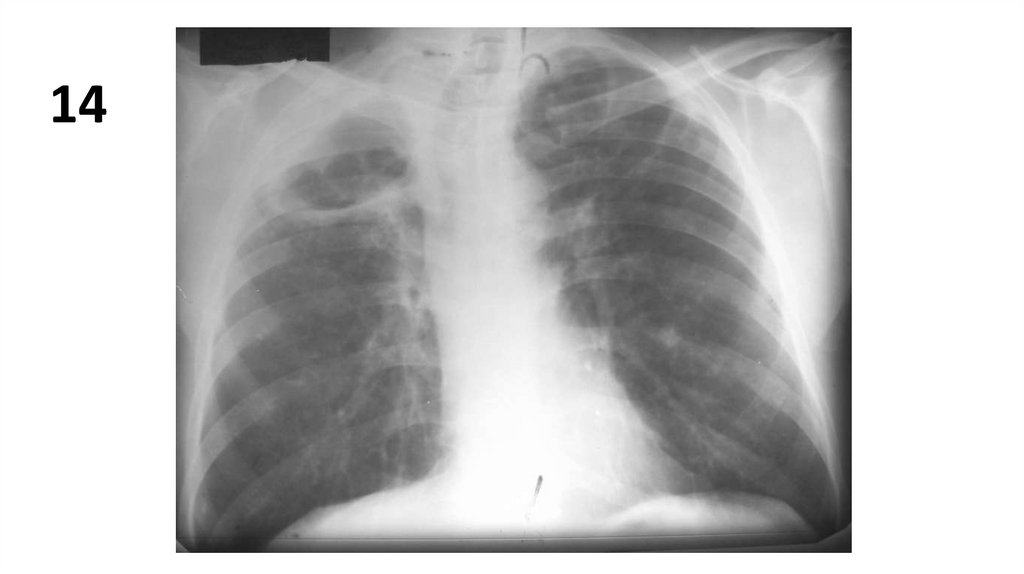

14.

14